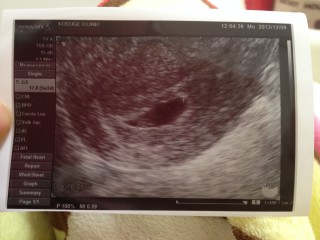

心臓が動いているのがはっきりわかりました。卵黄嚢も見えてます。 現在9.4ミリだそうです。 次は2週間後ですが、正直毎週見たいぐらいです!

6週1日で心拍確認でき1週間後!順調!